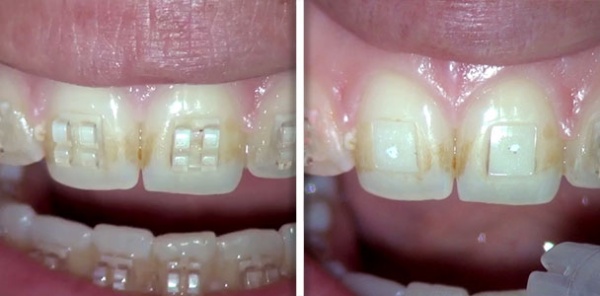

Orthodontic bracket removal

Courtesy of: Prof. Dr. Tosun Tosun

Laser source: Er:YAG (2940 nm)